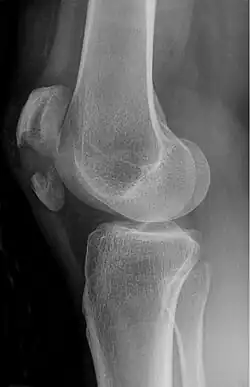

Transverse fracture of patella -

Comminuted fracture of patella -

The patella can break in various ways depending on the way it is injured, and into two or more pieces.[1] Types include transverse, the most common, with one fracture line;[5] marginal; osteochondral; and the rare vertical type, or stellate, where a direct compression force gives rise to a comminuted pattern.[5][7] Patella fractures can be further classified as displaced, where the broken ends of bone do not line up correctly and separate by more than 2mm, or undisplaced and stable where pieces of bone remain in contact with each other.[1][7] If fragments of patella bone stick out from the skin it is known as an open patella fracture, and closed if the overlying skin is intact.[1]